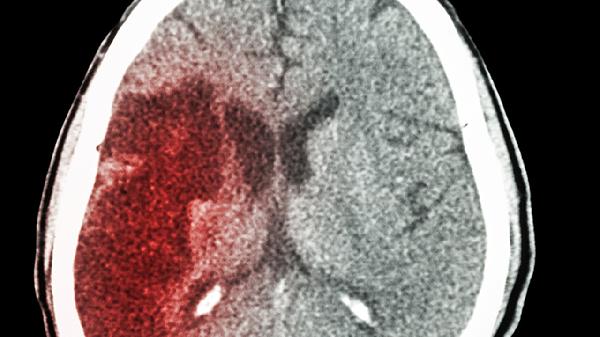

在急救車到達(dá)前維持上述處理措施,不可自行搬運或駕車送醫(yī)。腦出血患者需CT確診后由神經(jīng)外科專業(yè)團(tuán)隊進(jìn)行手術(shù)或藥物治療,包括血腫清除術(shù)、去骨瓣減壓術(shù)等。